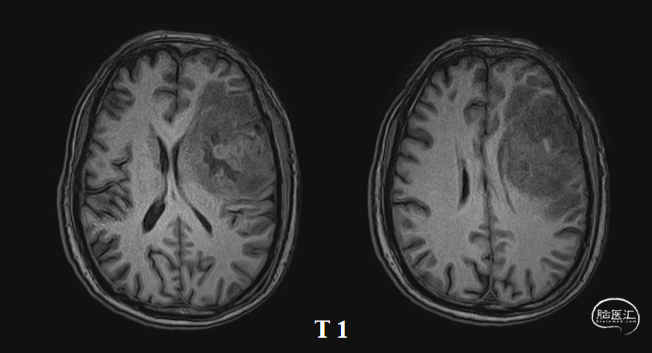

术前核磁(2020-03),左侧额岛叶肿块,信号不均匀,其内可见出血和坏死,占位效应明显,周围见水肿:图示。

入院前头MRI(2020-3):左侧额岛叶肿块,信号不均匀,其内可见出血和坏死,占位效应明显,周围见水肿。考虑左额岛叶肿瘤(高级别脑胶质瘤可能性大)。于2020年4月行左额岛叶占位性病变切除术。术中见肿瘤组织位于左侧额中回及额下回后部,大小约4m×5cm×5cm,呈烂鱼肉样,色灰红,质软,部分坏死,血运中等,边界不清,侵犯左侧岛叶向下挤压颞叶。显微镜下沿肿瘤周边胶质增生带完整切除肿瘤。术后48小时内复查头MRI平扫、加强,影像显示术腔边缘不规则线样强化,靠近放射冠及侧脑室壁强化明显,可疑少许残存。